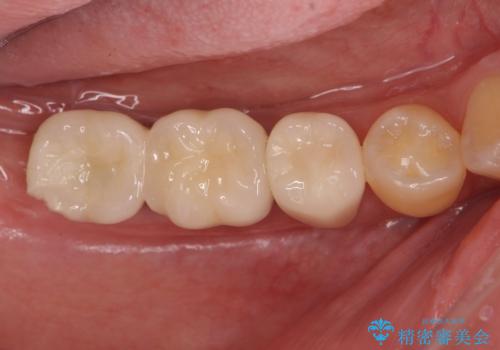

長期的な予後を見据えたインプラント治療

- 銀歯だらけの口腔内で将来歯がなくなるのではないかと不安になり、精査、治療を求めて来院されました。

歯周病や虫歯・強度の問題がありながらも無理やり残していた長期的な予後の見込めない歯を抜去し、インプラントを用いてしっかりと噛めるような口腔内環境の確立を目指します。

見た目が白くなり喜んでいただけただけでなく、しっかりとした噛めるようになり食事を不安なく楽しんでいただけるようになりました。